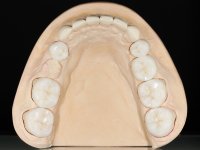

Realizado o diagnóstico e tomada a decisão quanto ao tratamento a executar, tornou-se importante definir qual a sequência de trabalho a adotar no sentido de conseguir a reabilitação da D.V.O. (V.D.O), de forma progressiva e equilibrada. Na primeira fase fez-se uma pré-impressão da arcada inferior com silicone tipo “putty” e em seguida realizou-se o preparo dentário de todo o sector posterior. O preparo para os overlays foi feito coronalmente à linha amelo cementaria no sentido de ser o mais conservador possível. A impressão foi feita com técnica de dupla mistura após afastamento gengival realizado com pasta de caulino. A provisória foi realizada com resina composta de polimerização dual. Em laboratório foram realizados os overlays após se ter aberto ligeiramente (1,5mm) a D.V.O. nos modelos montados em articulador semi-ajustável. Simultaneamente o sector antero-inferior foi encerado no sentido de acompanhar este aumento da D.V.O. Também foi confecionada uma chave de silicone translucido para posterior confeção dos provisórios antero-inferiores. Em boca foi primeiro realizada a provisionalização dos dentes anteriores utilizando resina composta previamente aquecida após preparação das superfícies dentárias para a adesão. Foi colocado o dique de borracha para promover o isolamento absoluto e posteriormente foram colados os overlays. Em laboratório foi realizada nova chave de silicone para confecionar os provisórios antero-superiores. Seguidamente em boca foram preparados os seis dentes antero-superiores após colocação do fio de afastamento gengival. Feita a preparação adequada das superfícies dentárias foi realizada a impressão com técnica de dupla mistura e a respetiva provisória. Em laboratório foram confecionadas 6 facetas feldespáticas num modelo de trabalho tipo “Geller”. A provisória foi removida e as facetas foram coladas em boca utilizando um isolamento relativo competente. Esta opção foi tomada em virtude de uma prévia experiencia negativa com a colocação do dique de borracha na mandibula. Após a colagem dos laminados antero-superiores foram dadas 12 semanas para avaliar a adaptação do paciente à nova situação e então iniciar a confeção das facetas antero-inferiores. Após colocação do fio de afastamento gengival. foram feitos os preparos dentários adequados e em seguida foi feita a impressão. Também foi feita a preparação do dente 3.4 que, entretanto, tinha sofrido uma fratura do overlay. As facetas e a restauração do 3.4 foram realizadas num modelo de trabalho tipo “Geller”. Após remoção da provisória, as facetas foram coladas em boca, utilizando um isolamento relativo pelas razões apontadas anteriormente. Após colocação do trabalho o paciente foi reabilitado por outros colegas com um implante na zona do 2.6 e substituição da coroa aparafusada sobre o implante colocado no local do 3.5. Posteriormente surgiram fraturas nos overlays dos dentes 4.7 e 3.7 que foram reabilitados com overlays em Zr.